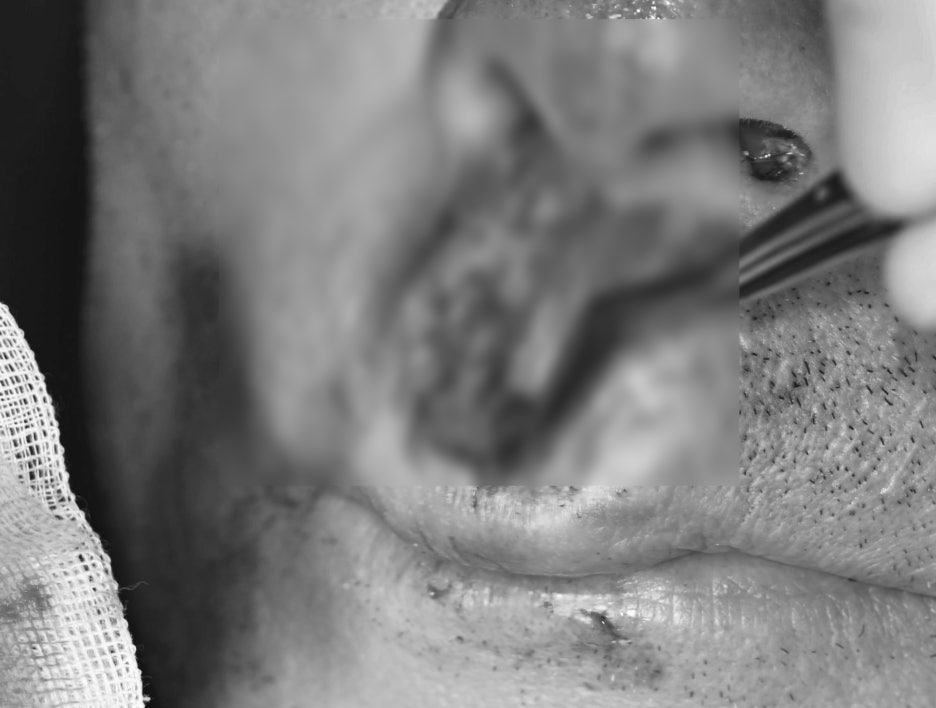

① Emergency laceration suturing

– After thoroughly disinfecting the torn areas of the lips and gums,

we sutured them.

– To prevent infection,

antibiotics and anti-inflammatory medication were used together.

Photo of the healed laceration area